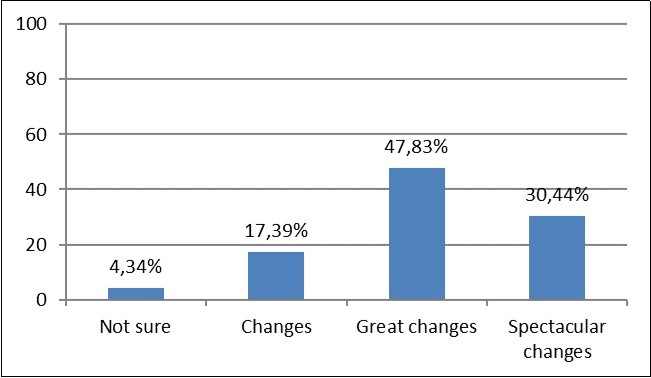

Of the 24 women who started this treatment, only one had to interrupt it. The interruption was not due to any side effect. Of the 23 women who received the 8 sessions, 1 (4.34%) reported not being sure of having noticed improvements in her skin; 4 (17.39%) reported noticing the changes, 11 (47.83%) reported noticing great changes and 7 (30.44%) reported spectacular changes (figure 3).

Figure 3.Skin changes reported by 23 women.

On the other hand, the results of the questionnaires carried out are very positive, with 78.27% of the patients reporting great or spectacular changes. However, the fact that these data have been obtained in a self-referential manner is subjective and far from an ideal condition. Future studies should confirm these findings, using objective methodologies to obtain the data. All in all, this type of information is very useful.